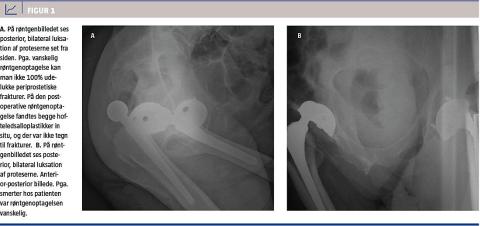

En 77-årig mand, som havde et alkoholoverforbrug, hjertesygdom og nedsat syn, blev indbragt som skadepatient med smerter i begge hofter efter at være faldet få trin på en trappe. Han havde i hhv. 1995 og 2007 fået bilateral THA. Angiveligt havde han ikke haft nogen tidligere luksationer. Ved den objektive undersøgelse fandtes højre underekstremitet at være indadroteret, og den venstre var flekteret. Trochanterpartiet var bagudtrukket på begge sider. Patienten var svært smerteforpint; smerterne stammede primært fra højre hofte. En røntgenoptagelse viste bilateral bagre dislokation uden tegn til frakturer (Figur 1). Røntgenoptagelsen var vanskeliggjort af svære smerter hos patienten. Fem timer efter ankomsten blev han anæsteseret, hvorefter proteserne kunne reponeres, begge ved vertikalt træk med patienten i rygleje. Proteserne blev testet og fundet stabile til 40 graders udadrotation på 90 graders fleksion og 0 graders adduktion. Repo-

sitionen blev dokumenteret ved peroperativ gennemlysning. Patienten blev mobiliseret frit efter opvågning, men havde dog behov for krykkestokke. Ved en røntgenkontrol sås begge proteser in situ; der var ingen frakturtegn og god stilling af protesekomponenterne. Patienten blev vurderet af hhv. en fysio- og e ergoterapeut. Bevægerestriktionerne blev genopfrisket, og der blev udleveret hjælpemidler, hvorefter han kunne udskrives efter en samlet indlæggelsestid på fire døgn. Der blev ikke foretaget yderligere opfølgning, men han blev genindlagt efter 11 mdr. og efter yderligere 14 dage med luksation på højre side. Begge gange pga. overskridelse af bevægerestriktionerne og uden traume. En efterfølgende ambulant kontrol mhp. vurdering af mulig revison af den højresidige THA mundede ud i fortsat konservativ behandling.